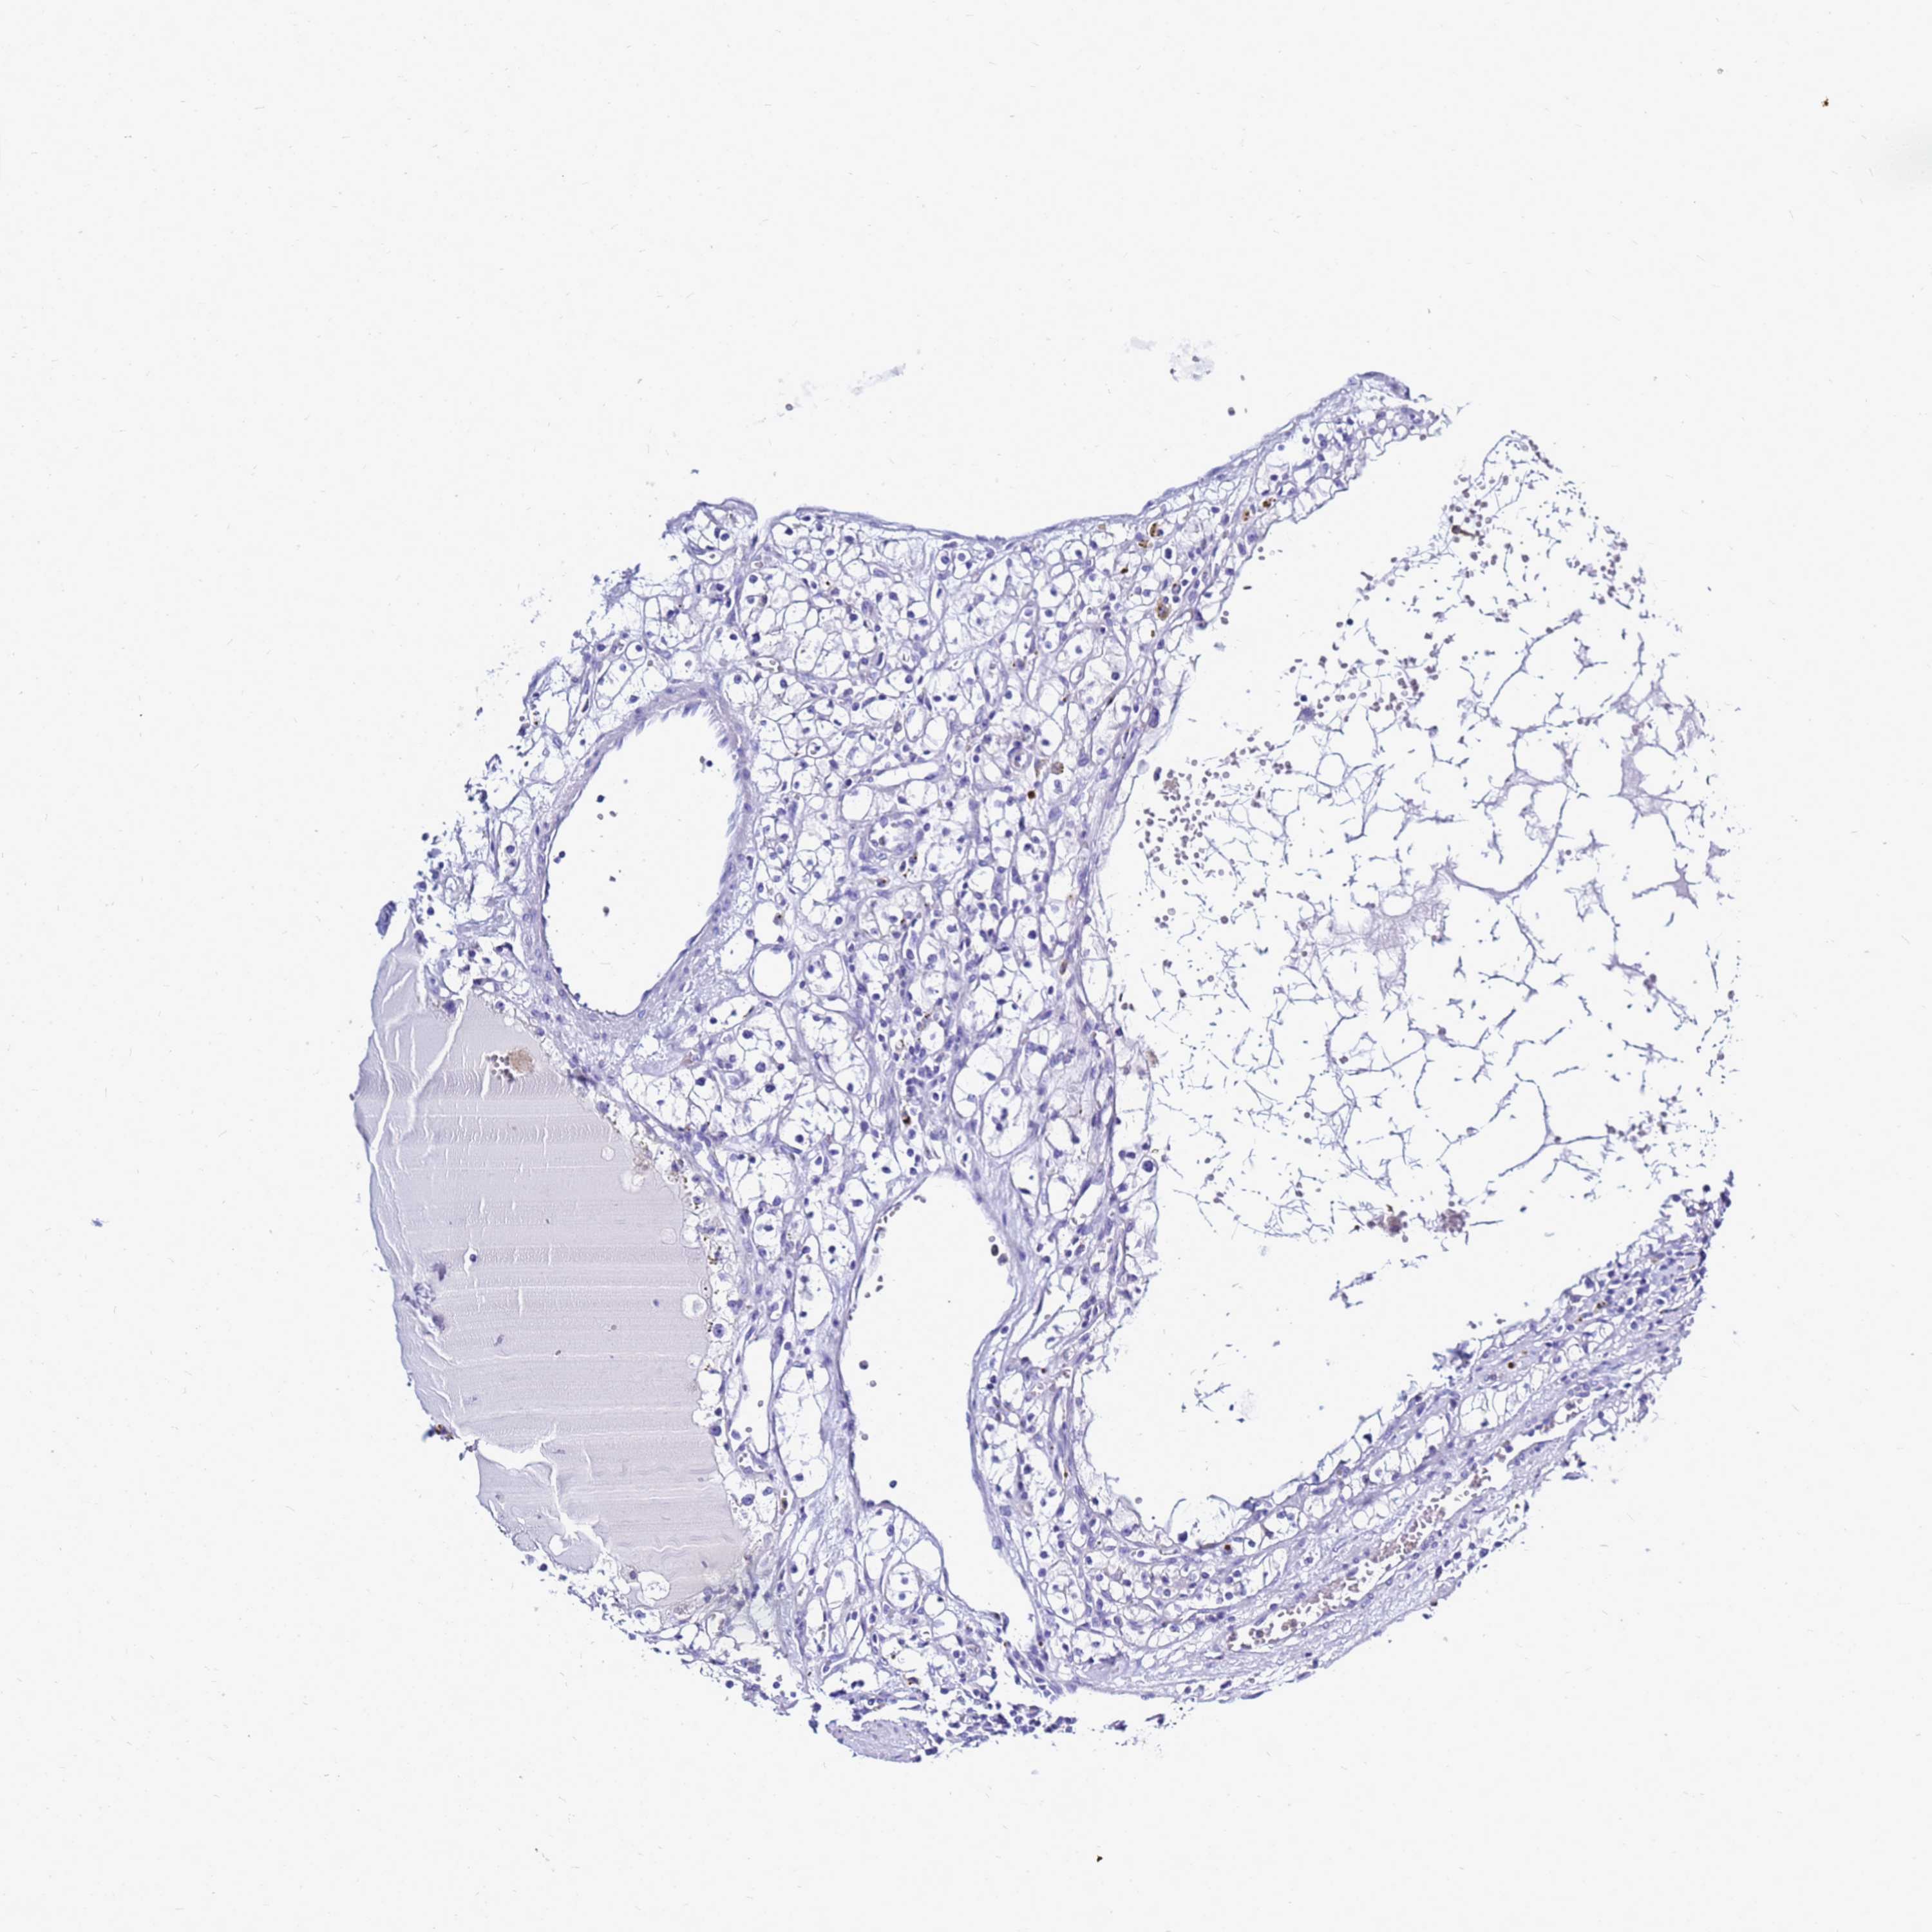

CANCER RENAL CANCER Show tissue menu

Renal cancer

Human cancer

Kidney chromophobe

Kidney renal clear cell carcinoma

Kidney renal papillary cell carcinoma